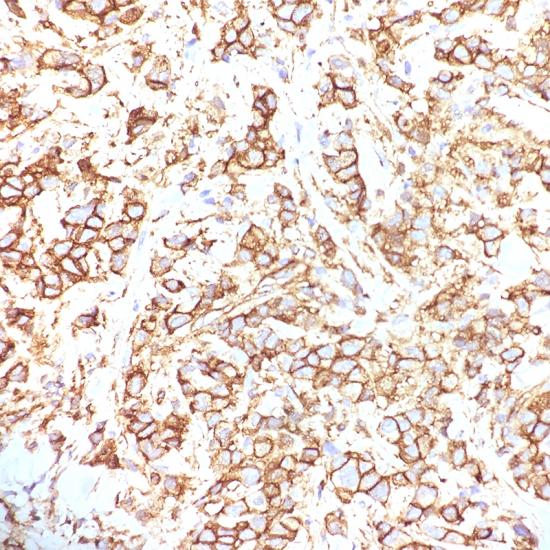

P120 catenin

• 陽性部位:

細胞漿/細胞膜

• 陽性對照:

乳腺癌

連接素家族包括α-catenin、β-catenin、γ-catenin和p120-catenin。p120在細胞膜旁的胞漿中與E-cadherin相連,不與肌動蛋白和α-catenin相連,如果缺乏E-cadherin,將會導(dǎo)致細胞漿內(nèi)p120的大量累積。在乳腺小葉癌中常顯示p120的大量蓄積,在乳腺導(dǎo)管癌中僅有少量細胞膜表達,而在細胞漿內(nèi)沒有p120的蓄積。此抗體可用于乳腺導(dǎo)管和小葉腫瘤的研究。